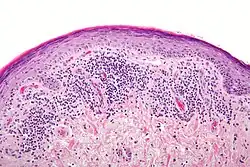

Histopathology

The histologic findings of oral LP can offer strong support for the diagnosis, but are not pathognomonic. Clinical correlation is required. Common histologic findings of oral LP include:[47]

- Parakeratosis and slight acanthosis of the epithelium

- Saw-toothed rete ridges

- Liquefaction (hydropic) degeneration of the basal layer with apoptotic keratinocytes (referred to as Civatte, colloid, hyaline, or cytoid bodies)

- An amorphous band of eosinophilic material at the basement membrane composed of fibrin or fibrinogen.

- A lichenoid (band-like) lymphocytic infiltrate immediately subjacent to the epithelium.

Nonetheless, interpreting the histopathological features of oral LP has been associated historically with high intra-observer and inter-observer variabilities.[66]